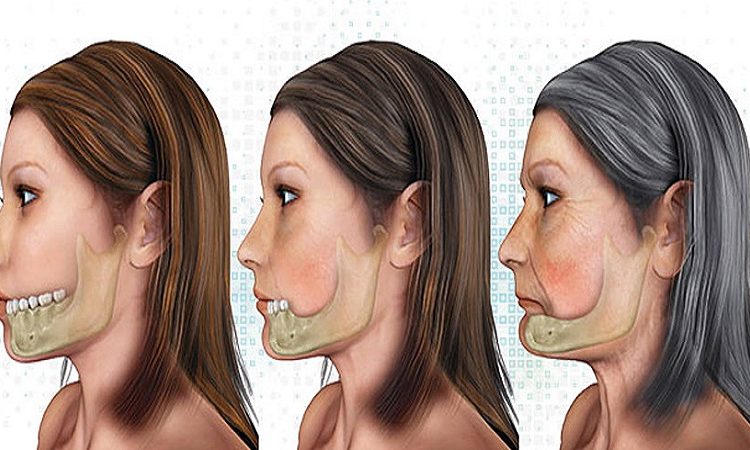

عوارض تحلیل و از دست رفتن استخوان فک چیست؟ از دست دادن استخوان فک میتواند: عوارض جدی برای سلامت دهان و دندانها و همچنین برای ظاهر و کیفیت زندگی فرد ایجاد کند. برخی از اصلیترین عوارض از دست دادن استخوان فک عبارتند از: ضعف و ناهنجاری ساختار فکها با تجزیه استخوان فک، فکها کمتر از

از دست دادن استخوان فک به چه معناست؟ تجزیه استخوان فک(کاهش تراکم استخوان فک) از دست دادن استخوان فک به معنای کم شدن یا تخریب استخوانهایی است که در فکهای بالا و پایین وجود دارد. این مسئله اغلب به عنوان “تجزیه استخوان فک” یا “کاهش تراکم استخوان فک” نیز شناخته میشود. وقتی که یک شخص